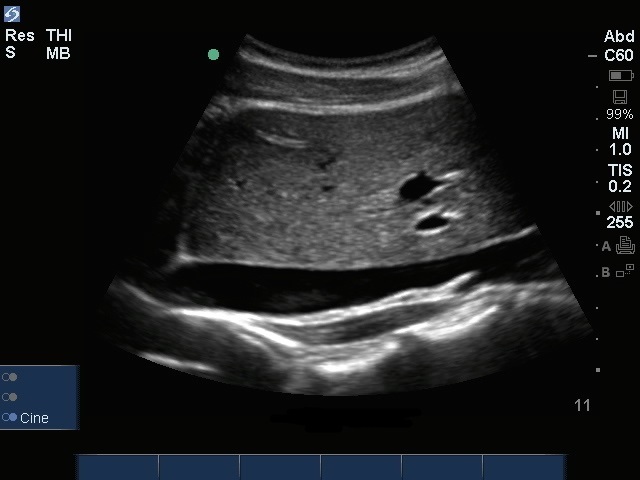

Imagen sagital de la vena cava inferior (VCI)